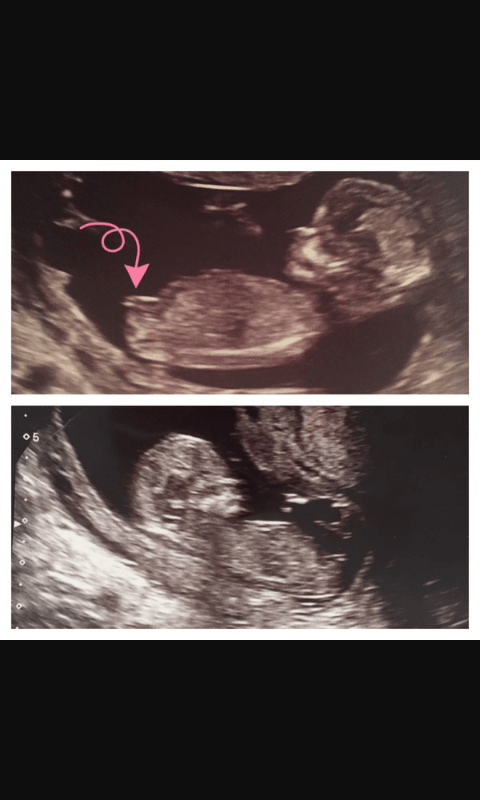

A oto i moje dziecię [emoji3]

A i dzidzia ma 7.5 cm, coś strasznie długi ten chlopczyk [emoji12] .

NT 1.70 to dobrze ?